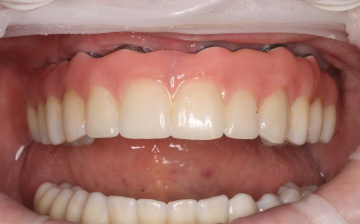

Ztráta zubu dnes neznamená ztrátu funkce ani estetiky.

Moderní implantologie umožňuje bezpečně a esteticky nahradit jednotlivé zuby i celé úseky chrupu – s maximálním komfortem a přirozeným vzhledem.

Cílem není jen funkční náhrada, ale přirozený výsledek, který odpovídá vaší osobnosti.

Definitivní zubní řešení

Po ukončení hojení následuje zhotovení definitivního zubního řešení – nejčastěji ve formě korunky, můstku nebo snímatelné náhrady na implantátech.

Každé řešení je navrženo individuálně, s důrazem na funkci, estetiku a dlouhodobou stabilitu.